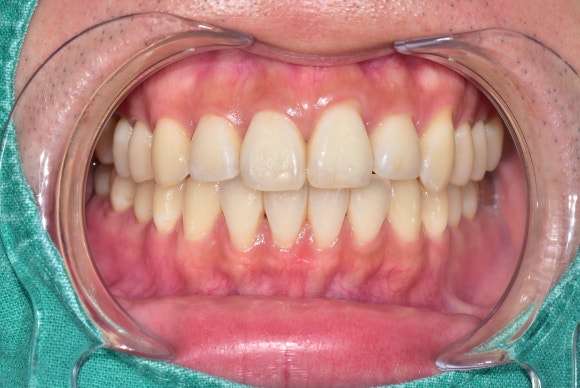

20250226

1회 시술 후 치아 색상이 한결 자연스러워진 것을 확인할 수 있습니다.

치아에 흰 반점이 있다고

무턱대고 치아를 삭제하거나

라미네이트같은 고가의 치료를 요하지 않는다는 것을 알려드리고자 본 포스팅을 기획하게 되었습니다.